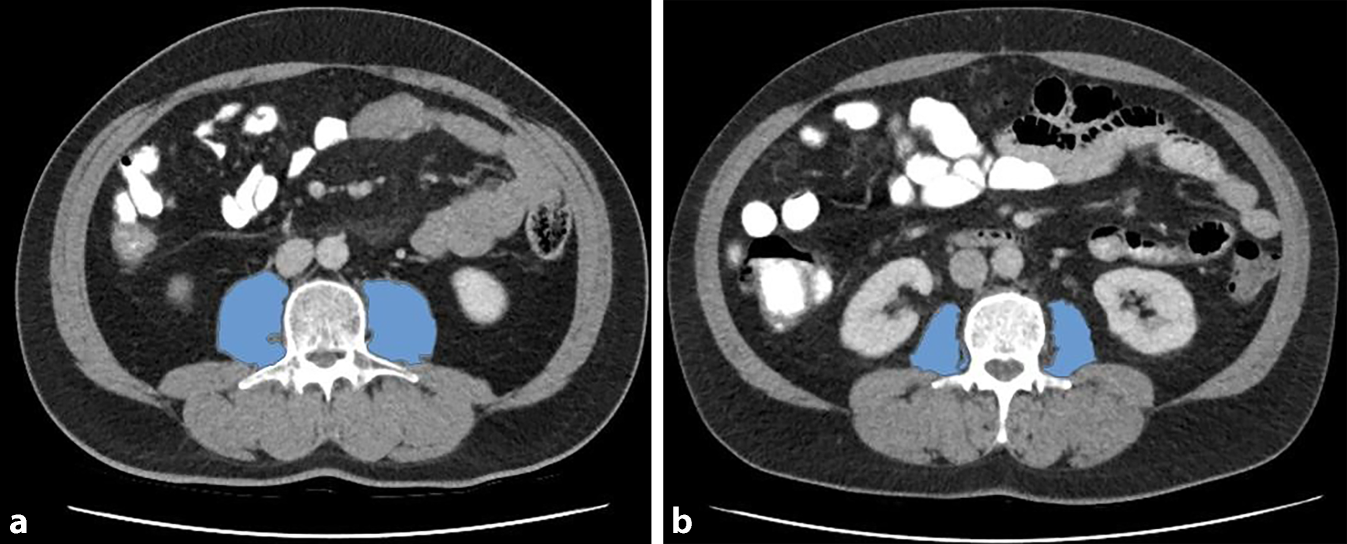

Messung der Psoasmuskulatur im CT

Alle computertomographischen (CT) Untersuchungen wurden in der portalvenösen Phase durchgeführt. Die Messungen am linken und rechten M. psoas wurden anhand von CT-Bildern auf der Höhe des 3. LWK in der Axialebene durchgeführt (Abb. 1). Ein Weichteilfenster von −30 bis 110 Hounsfield units (HU) wurde gewählt, um größere Gefäß- und Fettinfiltrationen der Muskeln von den nachfolgenden Berechnungen auszuschließen. Die Psoasmuskelflächen PMAlinks und PMArechts wurden addiert, um die gesamte Psoasmuskelfläche (PMAgesamt) zu berechnen. Aus dem Mittelwert der berechneten Abschwächung der Röntgenstrahlung (Röntgenopazität) beider Psoasmuskeln wurde die Röntgendichte (PMD) in HU berechnet (Abb. 1).

Abb. 1

a Männlicher Patient ohne Sarkopenie, PMI-Wert: 8,75 cm2 m−2; b männlicher Patient mit Sarkopenie, PMI-Wert: 4,30 cm2 m−2